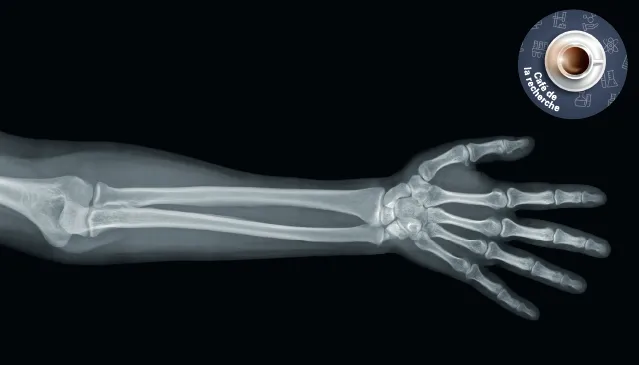

Mardi 3 octobre 2023, participez au Café de la recherche sur le thème : « Périostine, de la souris au diagnostic ». Ce café, animé par le Pr Serge Ferrari, médecin-chef du Service des maladies osseuses des HUG abordera l'importance de la périostine, une protéine présente dans divers tissus, dont l'absence entraîne principalement des problèmes dentaires et osseux. De plus, il discutera du développement d'un bioessai utilisant un fragment de périostine sérique pour diagnostiquer la fragilité osseuse, suite à sa découverte dans des modèles murins.